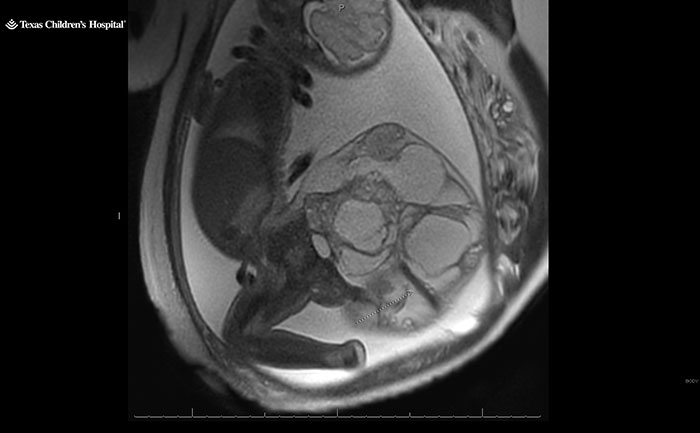

A 16-centimeter, four-pound (approximately 1.8-kilogram) fetal tumor was successfully removed from a baby’s tailbone. Born at 34 weeks, Adalida Tyler survived a sacrococcygeal teratoma tumor, a “very rare” condition that occurs in one in every 20,000 births.

A specialist subsequently diagnosed their unborn daughter with a sacrococcygeal teratoma instead, a rare fetal tumor that forms from the baby’s tailbone.

As they grow, the tumors can develop large blood vessels. “They basically steal the blood supply from the baby,” Dr. Nassr explained. “The heart of the baby needs to work very hard,” which, he said, can lead to heart failure.

On May 21, at 34 weeks, Kristin delivered Adalida via C-section. The little baby girl was born with the dreaded four-pound tumor, nearly two-thirds of her body weight.

Combined, the baby and tumor weighed more than 10 pounds (approximately 4.5 kilograms). Dr. Nassr recalled the tumor size being “a little bit smaller than a watermelon,” but larger than a cantaloupe.